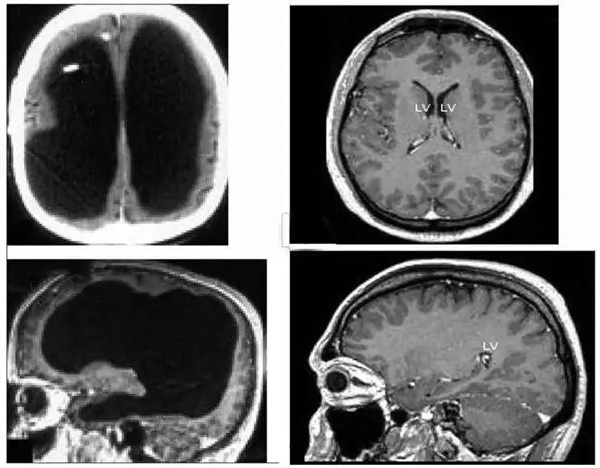

這位患者是法國(guó)人,前來(lái)就診時(shí) 44 歲,說(shuō)自己左腿無(wú)力已經(jīng)兩星期了。這聽(tīng)起來(lái)不是什么嚴(yán)重的大病,但詢問(wèn)病史后醫(yī)生得知,他在 6 個(gè)月時(shí)患上了原因不明的腦積水,為此進(jìn)行了引流,14 歲時(shí)又似乎因?yàn)橐饕l(fā)過(guò)左腿的運(yùn)動(dòng)失調(diào)和輕度偏癱。大概是考慮到舊病復(fù)發(fā)的可能性,醫(yī)生對(duì)他進(jìn)行了大腦 CT 和 MRI 掃描。C0R驛資訊

掃描的結(jié)果令所有人大吃一驚。他的大腦中央是一灘巨大的積水,腦子被擠壓到了邊緣薄薄一層。當(dāng)然嚴(yán)格來(lái)說(shuō)這也不是純水,而是腦脊液。正常人腦子內(nèi)有少量的腦脊液,不斷產(chǎn)生又不斷排出到循環(huán)系統(tǒng)里,保持總量穩(wěn)定,但這位患者腦內(nèi)的排水系統(tǒng)發(fā)生了障礙,進(jìn)多出少,導(dǎo)致液體越積越多。C0R驛資訊

左邊為這名法國(guó)男子的大腦,中間黑色部分都是腦脊液;右邊為正常人的大腦C0R驛資訊

這個(gè)人的腦子被擠壓得如此扭曲,所有的腦區(qū)都被壓扁了,可是不但此前沒(méi)有癥狀,還當(dāng)上了公務(wù)員且結(jié)婚生子。檢查發(fā)現(xiàn)他的全量表智商為 75,言語(yǔ)智商為 84,操作智商為 70,雖低于平均值,但也沒(méi)有低到離譜。C0R驛資訊